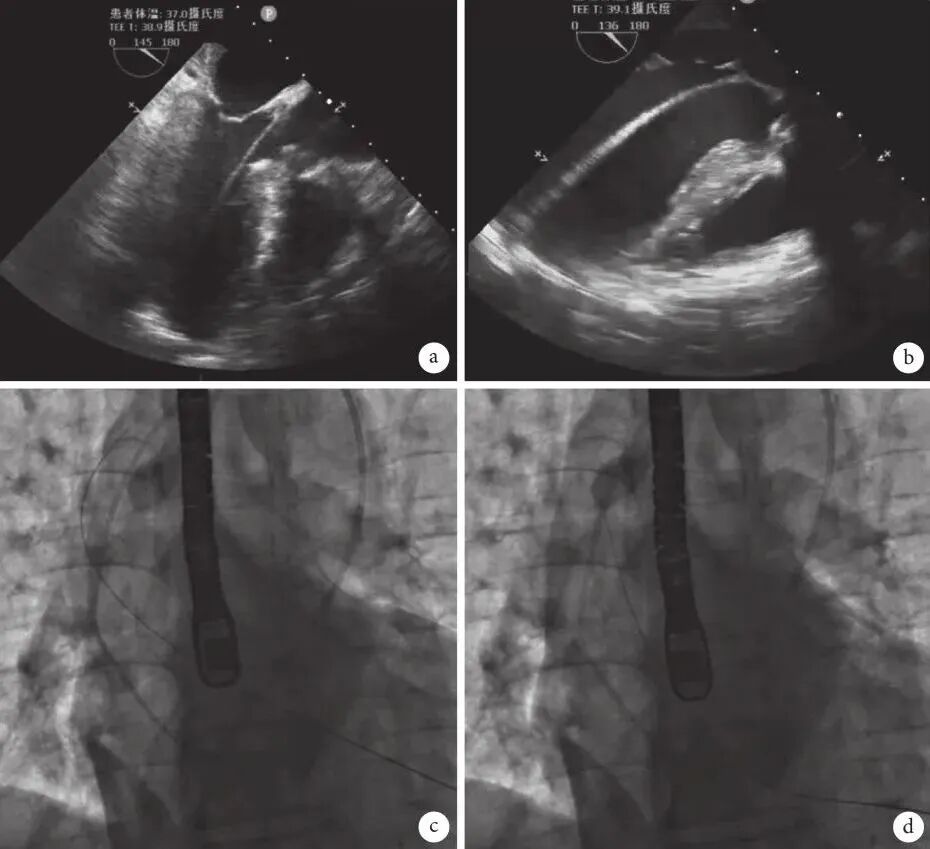

确定心尖位置对TA-TAVR的后续操作至关重要,在DSA下定位最具有指导意义,也可参考心表触诊,术前CT和术中经胸超声心动图(trans-thoracic echocardiography,TTE)辅助定位。在DSA透视下,将血管钳尖端置于体表左室心尖投影位置(图4),以该点为中点沿肋间走行方向做一3~5cm切口。游离皮下组织,沿肋间隙切开肌肉组织进入胸腔,避免损伤神经血管束。进入胸腔时可先开一小口用手指探查心尖位置是否位于该切口对应肋间,如位置不合适可重新选择上一肋间或下一肋间进入胸腔。肋骨撑开器撑开肋骨,显露心包,左肺通气一般不影响左室心尖部的暴露,如有影响可请麻醉医师调整呼吸机参数或用湿纱布将其压向背侧。心尖有时正对肋骨而非肋间隙,此时可通过切开心包的位置对心尖位置做适当调整。例如心尖位于切口所在肋间隙足侧,我们可以将心包切口靠足侧,通过悬吊足侧心包将心尖稍向头侧牵拉。如心尖位置仍不满意,可在心脏后垫小纱球来调整心尖位置至切口正中,心尖部随心脏收缩而旋转的心脏裸区为最佳位置,通常围绕该区域缝合荷包。特殊情况下心尖荷包部位难以确认,可通过TEE引导,手指按压心脏来确定心尖位置。大部分患者的心尖裸区显露良好,部分患者心尖被脂肪覆盖,需要先分离或去除心尖部位脂肪组织,彻底显露心尖的肌性组织(图5)。

图片

图4 数字减影血管造影(DSA)下定位心尖位置

(白色箭头示在DSA下将血管钳尖端置于体表左室心尖投影位置)

图5 心尖显露示意图

(a:切开位置选择示意图;b:悬吊心包后显露心尖区域;c、d:如心尖区域被脂肪覆盖,则分离或去除心尖部位脂肪组织,彻底显露心尖的肌性组织)